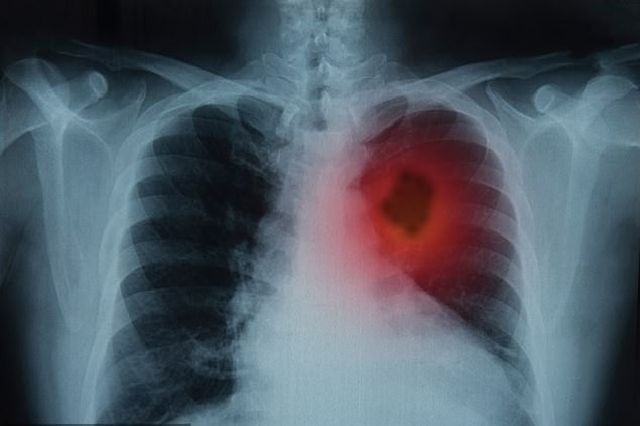

Bổ sung vitamin C có thể khiến các khối u ung thư phát triển

Bổ sung vitamin vốn được cho là có tác dụng nuôi dưỡng cơ thể, nhưng nghiên cứu mới, vừa được công bố trên tạp chí y khoa Journal of Clinical Investigation, đã phát hiện điều này có thể khiến các khối u ung thư phát triển.